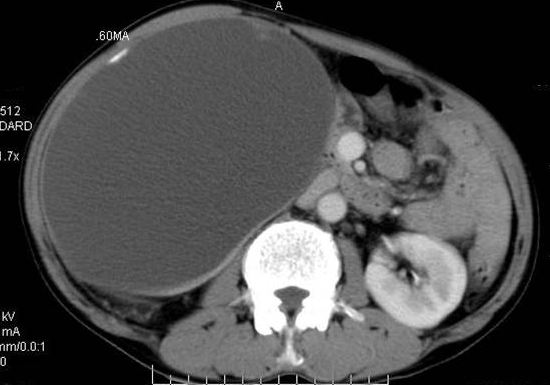

男性 60岁,腹部肿块4年余,肿块逐渐增大,活动性差,无血尿。

门脉期

右肾脏巨大囊样影、囊壁有钙化,囊样影轻度强化有软组织成份。不除外畸胎瘤可能。

巨大囊性肿块,囊壁较厚有强化,有团片状钙化,病灶内下方灶内见片絮状高密度影,增强有轻中度强化,考虑囊性肾癌可能性大

右肾上部巨大的囊实性影,实性部分轻度强化。壁有钙化。考虑右肾囊腺癌。右肾盂积水。